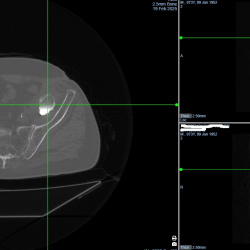

Здравствуйте, уважаемые коллеги. Женщина 64г, боли в левом тбс. Собираюсь описать как множественные обызвествления в мягких тканях, вероятнее олеогранулемы. Поделитесь мыслями, пожалуйста...

26.02.2025 - 14:42